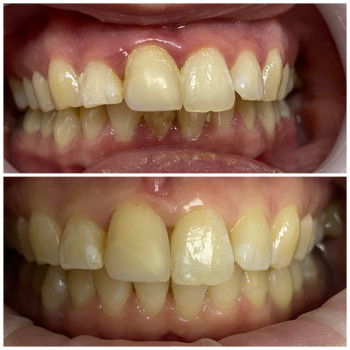

Лікування пародонтиту від 1 до 4 ступеня тяжкості у Хмельницькому Пародонтит – це запальне захворювання ясен і тканин, що утримують зуби. Без лікування воно прогресує від початкового нальоту й кровоточивості до серйозної втрати кісткової тканини та рухливості зубів. У нашій клініці ми проводимо комплексне лікування пародонтиту будь-якої стадії – від 1 до 4 ступеня тяжкості. ✔️ 1 ступінь – професійна гігієна, усунення нальоту, навчання догляду ✔️ 2 ступінь – кюретаж ясенних кишень, лікування запалення ✔️ 3 ступінь – комплексна терапія, шинирование, відновлення тканин ✔️ 4 ступінь – хірургічні методи, імплантація та протезування при втраті зубів Ми використовуємо сучасні методи: ультразвукову чистку, Air Flow, закритий кюретаж. Регулярне звернення до пародонтолога дозволяє зупинити прогресування хвороби, зберегти власні зуби та повернути здоров’я ясен. 👉 Запишіться на консультацію та лікування пародонтиту у Хмельницькому – відновіть здоров’я ротової порожнини на будь-якій стадії захворювання!